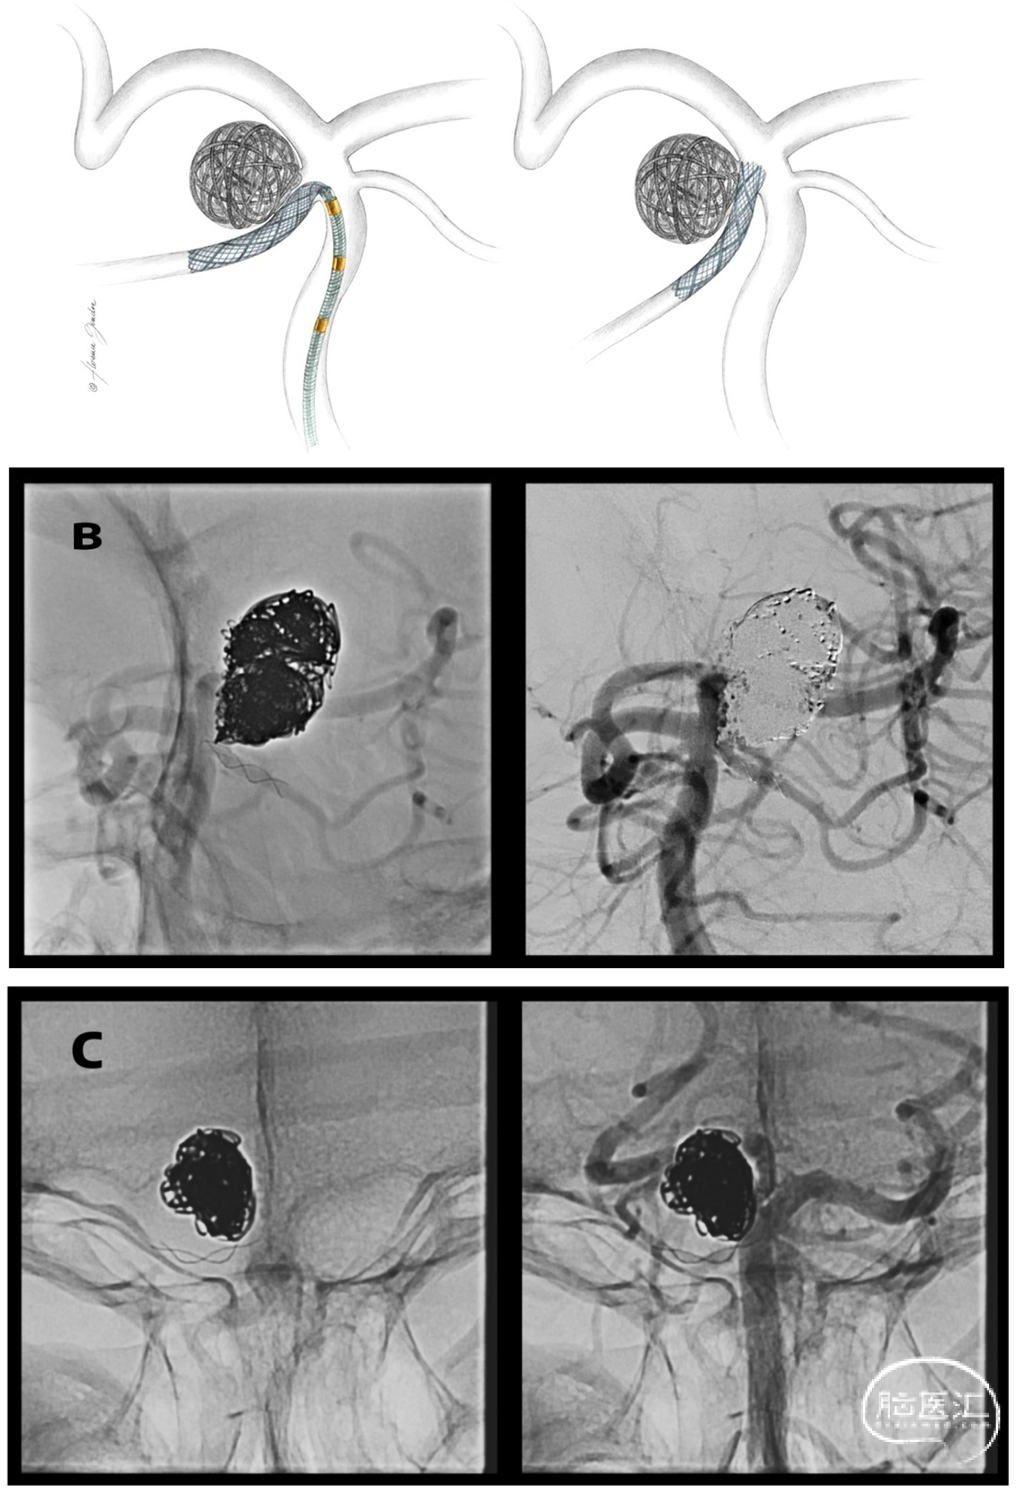

3. 编织支架T型置入——两种构型

● Half-T——首选策略(40/55)

✔ 支架先部分远端释放,逐步调整位置,直到近端节段完全覆盖瘤颈,这是实现精准贴壁、优化瘤颈覆盖的核心步骤

✔ 解决SUCA-BA锐角贴壁问题

● Complete-T

✔ Half-T基础上,额外从PCA向BA释放第二枚支架,重建分叉

✔ 术中判断弹簧圈不稳定、瘤颈广泛累及BA/PCA

术中决策原则:构型选择实时决定,依据球囊辅助下弹簧圈稳定性及瘤颈覆盖效果;注意静态3D与术中动态球囊造影的瘤颈形态差异。

Figure 2. A, Repositioning of the braided stent to achieve optimal coverage of the aneurysm neck, with slight protrusion into the basilar artery. B, Unsubtracted and subtracted angiographic images demonstrating optimal neck coverage with the Half-T stenting technique. C, Example of a superior cerebellar artery (SUCA) aneurysm involving the origin of the posterior cerebral artery (PCA), showing good coverage of the aneurysm neck.